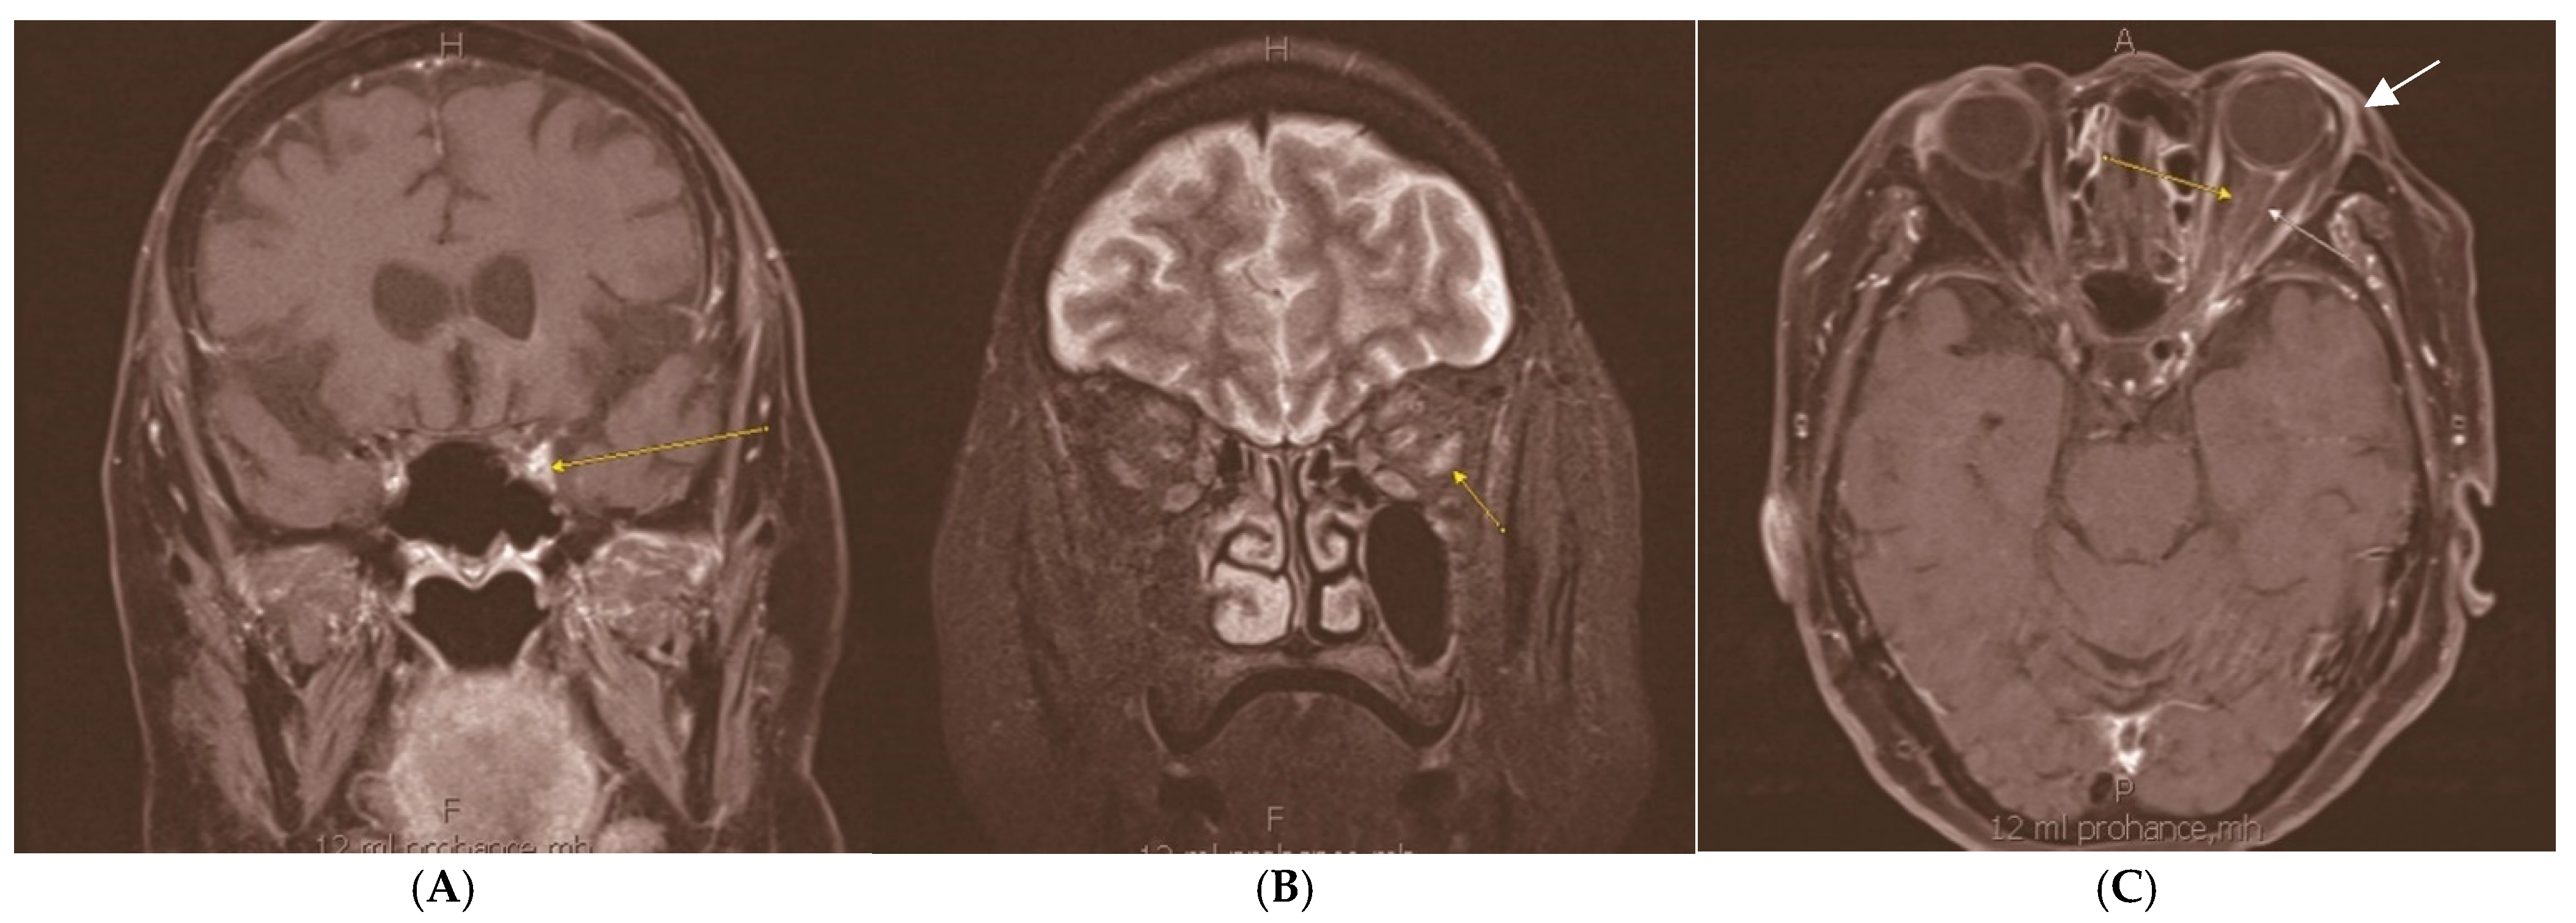

Orbital Neurolymphomatosis in Patient with CNS Lymphoma